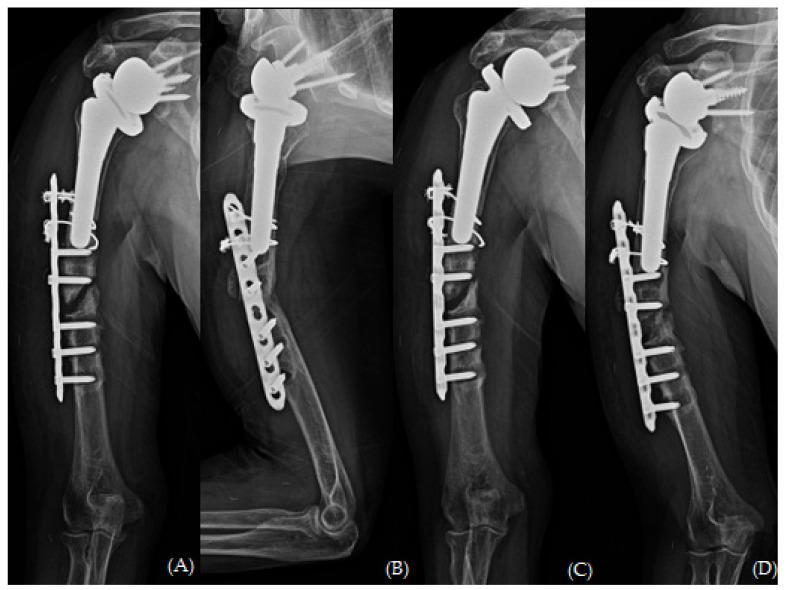

Periprosthetic fractures are a serious complication of joint replacement surgery. With the growing prevalence of reverse total shoulder arthroplasty (RTSA), the incidence of relatively uncommon periprosthetic humeral fractures has increased. Here, we present the unique case of a 74-year-old woman who developed atrophic non-union after plate osteosynthesis for a periprosthetic fracture associated with RTSA. Fixation failure was evident 3 months after the surgical intervention; the patient underwent a 3-month course of arm sling immobilization. However, bone resorption continued, and varus angulation of the fracture developed. In this case, surgical strategy involved the use of long proximal humerus internal locked system plate (DePuy Synthes, Paoli, PA, USA), augmented with autologous iliac bone graft and allogenic humerus structural bone graft with the "bamboo support technique", fixed with Cable System (DePuy Synthes, Paoli, PA, USA). No reports have addressed the management of failed periprosthetic fractures using allogeneic humeral strut bone grafts. This report aims to fill the gap by presenting a novel surgical technique for the management of periprosthetic fractures associated with RTSA in case of treatment failure.

假体周围骨折是关节置换手术的一种严重并发症。随着反式全肩关节置换术(RTSA)的日益普及,相对罕见的假体周围肱骨骨折的发生率有所增加。在此,我们报告一例独特病例,一名74岁女性在因与RTSA相关的假体周围骨折行钢板内固定术后发生萎缩性骨不连。手术干预3个月后固定失败;患者接受了为期3个月的手臂吊带固定治疗。然而,骨吸收仍在继续,骨折出现内翻成角。在该病例中,手术策略包括使用肱骨近端加长锁定系统钢板(美国宾夕法尼亚州波利市DePuy Synthes公司),采用“竹节支撑技术”辅以自体髂骨移植和同种异体肱骨结构性骨移植,并使用线缆系统(美国宾夕法尼亚州波利市DePuy Synthes公司)进行固定。尚无关于使用同种异体肱骨支撑骨移植治疗失败的假体周围骨折的报道。本报告旨在通过介绍一种治疗失败情况下处理与RTSA相关的假体周围骨折的新颖手术技术来填补这一空白。